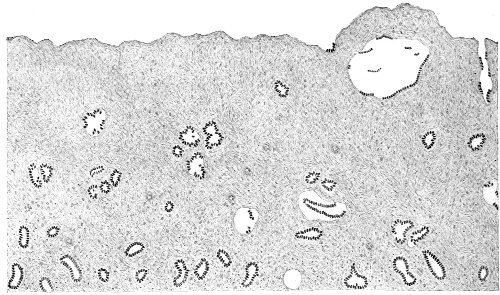

Several varieties of acute vaginitis may be recognized—the simple, the granular, the senile, and the emphysematous. It is unusual to find the entire surface of the vagina involved. The disease is confined to areas or patches separated by healthy tissue.

In simple vaginitis the inflamed membrane remains smooth.

In granular vaginitis, which is the variety usually seen, the papillæ are infiltrated with small cells, and are much enlarged, so that the inflamed surface has a granular appearance.

Senile vaginitis is due to infection of portions of the vaginal mucous membrane that have lost their epithelium as a result of the atrophic changes of old age. This disease occurs in patches of various size, sometimes presenting the character of ecchymosis; in other cases the 50 patches have altogether lost the epithelium, and permanent adhesions may take place between areas which are brought in contact. This form of vaginitis has also been called adhesive vaginitis. It is said that a similar condition may occur in children.

The emphysematous form of vaginitis occurs in pregnancy. The vaginal walls are swollen and crepitating. The gas is contained in the meshes of the connective tissue.

Acute vaginitis is accompanied by dull pain and a sense of fulness in the pelvis. The discomfort is increased by standing, walking, defecation, and urination. There is a free discharge of serum or pus, which may be tinged with blood. The character of the discharge depends upon the variety and the period of the disease. Inspection, which can best be made through the Sims speculum, with the woman in the Sims or knee-chest position, shows the characteristic lesions of inflammation of the mucous membrane.

Acute vaginitis, if neglected, may pass into the chronic form. It usually lingers in the upper part of the vagina, in the fornices, especially in vaginitis of gonorrheal origin. By careful inspection we find here one or more granular patches of inflammation, which cause a vaginal discharge from which man may be infected, and from which infection of the upper portion of the genital tract, the uterus, and the Fallopian tubes may be derived.